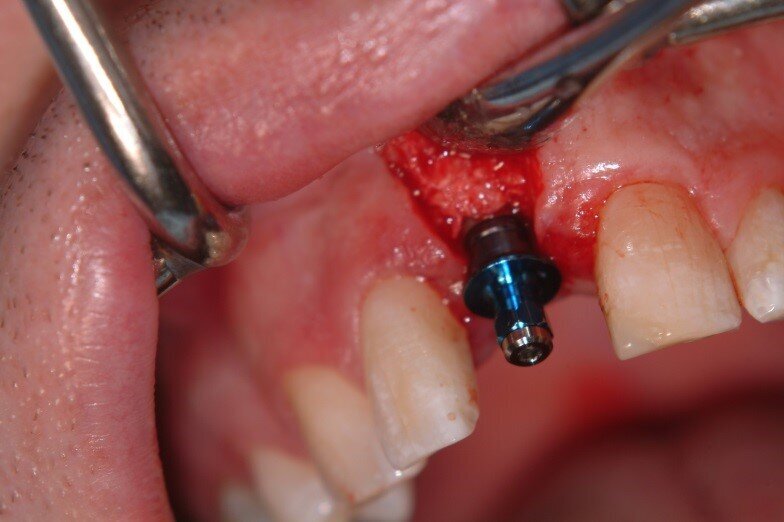

1. The graft was left to mature for 6 months then a full thickness papillae preserving flap was used to access the site, revealing excellent regenerated bone

2. A 15mm Full Osseotite straight sided external hex implant (Biomet 3i) was placed with an insertion torque of 45Ncm. Because the implant was largely in regenerated bone, immediate restoration was not attempted. No additional grafting material was needed. (Fig. 12, 13)